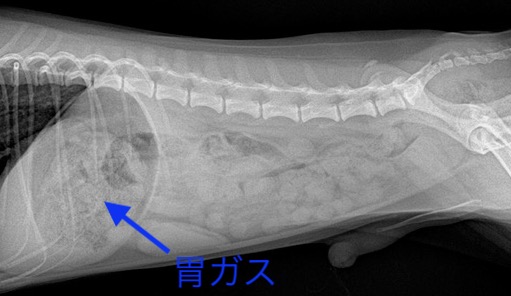

『治療2ヶ月後』:胃ガスが減ってきており、改善傾向になります。

嘔吐の頻度も減ってきており、レントゲン検査での効果も認められたため、

食事治療が奏功していることが分かりました。